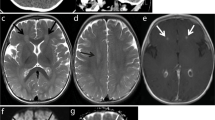

Exome sequencing identified patients 1 and 7 to carry the same heterozygous TLR3 variation (rs147431766; chr4:187005064C>T ENSG00000164342:ENST00000296795:exon4:c.C2224T:p.L742F) which is enriched in the Finnish population (allele frequency (AF) 0.01621 in Finnish population) compared to more heterogenous European population (AF 0.0007 in European non-Finnish, Genome Aggregation Database; gnomAD; https://gnomad.broadinstitute.org/), and has not been described in any human patients. Regardless, the p.L742F variation is significantly enriched in our patient cohort (29%, p = 0.0195) compared to general Finnish population. Other two patients, patients 2 and 3, are heterozygous for a common TLR3 p.L412F variation (rs3775291, AF 0.324487 in Finnish population), but this variant showed no enrichment in our patients. The TLR3 variants were validated by Sanger sequencing in all patients. The L742F variant found in our PUUV HFRS patients is shown in Fig. 1g. Figure 1 g also illustrates previously characterized TLR3 mutations associated with HSE, severe influenza, and other viral infections [17,18,19,20].

TLR3 mRNA expression levels were determined by RT-qPCR, as normalized to wild-type (WT) relative expression levels, in P2.1 TLR3-deficient fibrosarcoma cells without transfection (NT) or transfected with empty vector (EV), HA-tagged TLR3 WT, L742F (p.Leu742Phe), R867Q (p.Arg867Gln), or E746X (a). IFNL1 (IL29) induction by poly(I:C) stimulation, as normalized to wild-type (WT) fold induction level, in P2.1 cells not transfected (P2.1) or stably transfected with empty vector (P2.1+EV), HA-tagged TLR3 WT, L742F, R867Q, or E746X (b). Production of IL-29 (c and d), and IL-6 (e and f) in SV40-fibroblasts from three healthy controls (C1, C2, C3), P1, and a TLR3−/− HSE patient, 24 h after stimulation with 1, 5, or 25 μg/ml poly(I:C) (c and e), or with 25 μg/ml poly(I:C) in the presence of lipofectamine (poly(I:C)+lipo; d and f), or lipofectamine alone, as assessed by ELISA. Schematic structure of the human TLR3 gene and protein, featuring the leader sequence (L), leucine-rich repeats (LRRs) of the ectodomain, transmembrane domain (TM), linker region (LR), and Toll/IL-1 receptor (TIR) domain. Roman numerals indicate the coding exons. Previously reported mutations found in patients with HSE patients (E110K, L297V, L360P, P554S, G743D, R811I, R867Q), severe influenza (F303S, P554S, P680L) or Varicella zoster virus infection (L199F, R867X), that have been previously experimentally characterized (F303S, L360P, P554S, P680L, G743D, R811I, R867Q, R867X) or not (E110K, L199F, L297V) are shown in blue. The L742F mutation found in the two patients with complicated Puumala hantavirus infection is shown in red (g)

The L742F TLR3 Protein Is Severely Hypomorphic In Vitro

We aimed to analyze the effect of the TLR3 L742F variant in the TLR3-deficient P2.1 fibrosarcoma cell line, which does not produce detectable amounts of TLR3 protein and does not respond to the dsRNA mimic polyinosinic:polycytidylic acid (poly[I:C]) [32]. To do so, we generated cell lines stably transfected with empty plasmid or with plasmids containing C-terminally HA-tagged WT and mutants TLR3 cDNAs. In P2.1 cells expressing WT TLR3, the production of IFNL1 mRNAs was induced after poly(I:C) stimulation, whereas cells expressing the L742F displayed low poly(I:C)-stimulated induction of IFNL1 mRNA, like those expressing the previously reported R867Q allele, while the previously reported E746X allele displayed no induction of IFNL1 (E746X) (Fig. 1a, b). We chose not to analyze activity of the TLR3 p.L412F variation, as this variant is not enriched in our patients and it is thoroughly analyzed by previously studies in different conditions. [27,28,29,30,31]

Impaired Responses to Poly(I:C) in Patient Fibroblasts Heterozygous for TLR3 L742F

We further tested whether heterozygosity for the TLR3 L742F mutation is related to an AD TLR3 deficiency at the cellular level. Human dermal fibroblasts respond to extracellular poly(I:C) stimulation in a TLR3-dependent manner [17, 26, 33]. We studied the response to poly(I:C) in SV40-immortalized skin fibroblasts (SV40-fibroblasts) from P1 (L742F/WT), three healthy individuals and a HSE patient with AR complete TLR3 deficiency (TLR3−/−, due to compound heterozygous P554S and E746X mutations) [26, 33] (Fig. 1c–f). The fibroblasts from the three healthy controls produced increasing levels of IFN-λ and IL-6 after 24 h of stimulation with increasing concentrations of poly(I:C), whereas the production of the cytokines was impaired in P1 TLR3 L742F/WT and abolished in TLR3−/− fibroblasts.